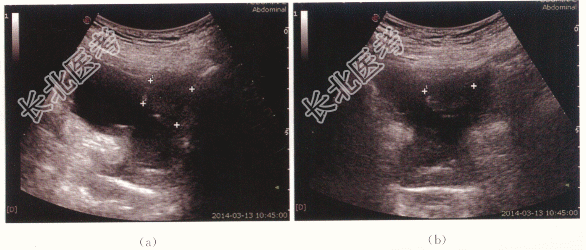

患者,男性,78岁,因“无痛性肉眼血尿10天”就诊。

尿隐血:(++)。

二、影像资料

- 简答题1、若确诊为膀胱癌,其特征声像图表现有哪些?